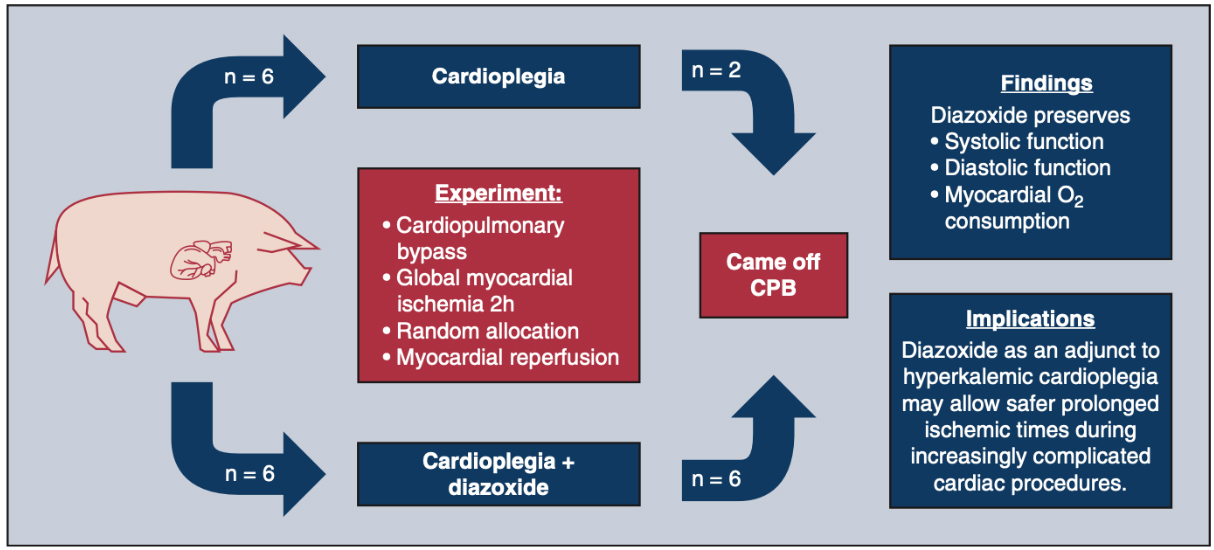

An early study in 2005 comparing diazoxide to control in a porcine model found that diazoxide did not provide cardioprotection (infarct size and systolic function) after myocardial ischemia[133]. The authors acknowledged that their results were incongruent with others’ findings and postulated that this could be due to preconditioning effects of anesthetics or an incorrect dose of diazoxide. Recent studies have been more promising. In an isolated mouse heart model, adding diazoxide to cardioplegia led to improved diastolic function following a period of global ischemia[134].Two subsequent studies were conducted in swine models. In the first, swine treated with hypothermic, hyperkalemic cardioplegia with diazoxide (single dose) prior to a 2-h global ischemic period were found to have improved systolic and diastolic ventricular function compared to cardioplegia alone [Figure 2][135]. In the second, swine underwent 30 min of occlusion of the left anterior descending artery prior to 2 h of global ischemia protected with cardioplegia or cardioplegia with diazoxide (dosed every 20 min) [Figure 3][136]. Compared to cardioplegia alone, animals that received diazoxide had decreased myocardial stunning and shortened time to separate from cardiopulmonary bypass [Figure 4][136]. These studies provided some of the most convincing preclinical data to date that diazoxide will be beneficial as an additive to cardioplegia in humans undergoing cardiac surgery requiring global ischemia. It is important to acknowledge the limitations of the translational models that have been widely used to study KATP channels and cardioprotection. These models may not provide sufficient confidence to translate to human pathophysiology. These limitations highlight the importance of randomized clinical trials in humans before widespread adoption.

Figure 2. Summary of the benefits with use of KATP channel opener diazoxide in a translational swine model of hypothermic cardioplegic arrest and prolonged global ischemia similar to a prolonged global ischemia model for clinical cardiac surgery. Swine undergo cardiopulmonary bypass and prolonged global ischemia of the heart via placement of aortic cross clamp (120 min) with one dose of cardioplegia, similar to clinical cardiopulmonary bypass. Animals are randomized to one of two groups: cardioplegia alone or cardioplegia plus diazoxide. Animals who underwent cardioplegia plus diazoxide in this model had preserved systolic and diastolic function, suggesting that adding diazoxide to cardioplegia may result in improved outcomes[135]. This model simulates the clinical situation of a patient presenting to the operating room for a prolonged global ischemic period for cardiac surgery protected with one dose of cardioplegia[135]. This figure is used with permission from Elsevier (obtained September 4, 2023, license number 5621921258491)[135]. CPB: Cardiopulmonary bypass.